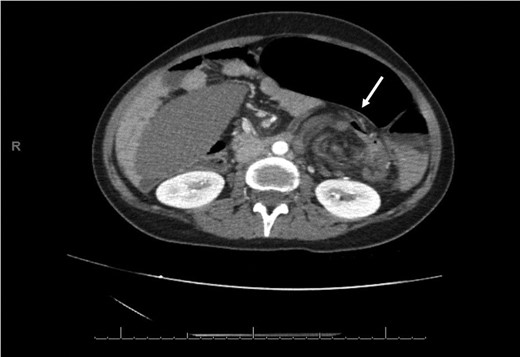

Laboratory investigation showed a white blood cell count of 15.13 × 103/UL, (mainly neutrophilia of 90.3%), a hemoglobin level of 9.4 g/dL, and a platelet count of 189 × 103/UL. The other biochemical parameters including liver enzymes were normal apart from a trace of jaundice, with total Bilirubin of 2.43 mg/dL and direct Bilirubin of 0.45 mg/dL. Chest X-ray showed bowel loops at the splenic fossa (Fig. 1). An initial diagnosis of a torted ovarian cyst was made. A pelvi-abdominal ultrasound revealed normal adnexa but a right-sided soft pelvic-abdominal mass with the absence of a splenic shadow at the left hypochondrium. Subsequently, CT scan of the abdomen and pelvis revealed a large right-sided infarcted spleen of 30 × 16 × 10 cm3 (Fig. 2) and a ‘whirl sign’ of the splenic pedicle (Fig. 3). Furthermore, CT scan showed signs of portal hypertension (Fig. 4) associated with mesenteric varices (Fig. 5). The patient subsequently underwent a surgical exploration.

An axial CT of the upper level of the abdomen shows a corkscrew-like soft tissue density (white arrow) indicating twisted splenic vessels surrounded by peritoneal ligaments and fats forming a whirly appearance with alterative lucent and dense bands (a whirl sign), is a pathognomonic CT findings of torsion.

As the diagnosis of torsion of a wandering spleen is challenging, CT scan imaging showing the characteristic sign of a ‘whirled appearance’ of the splenic pedicle is considered the preferred modality for diagnosis of this condition [9].